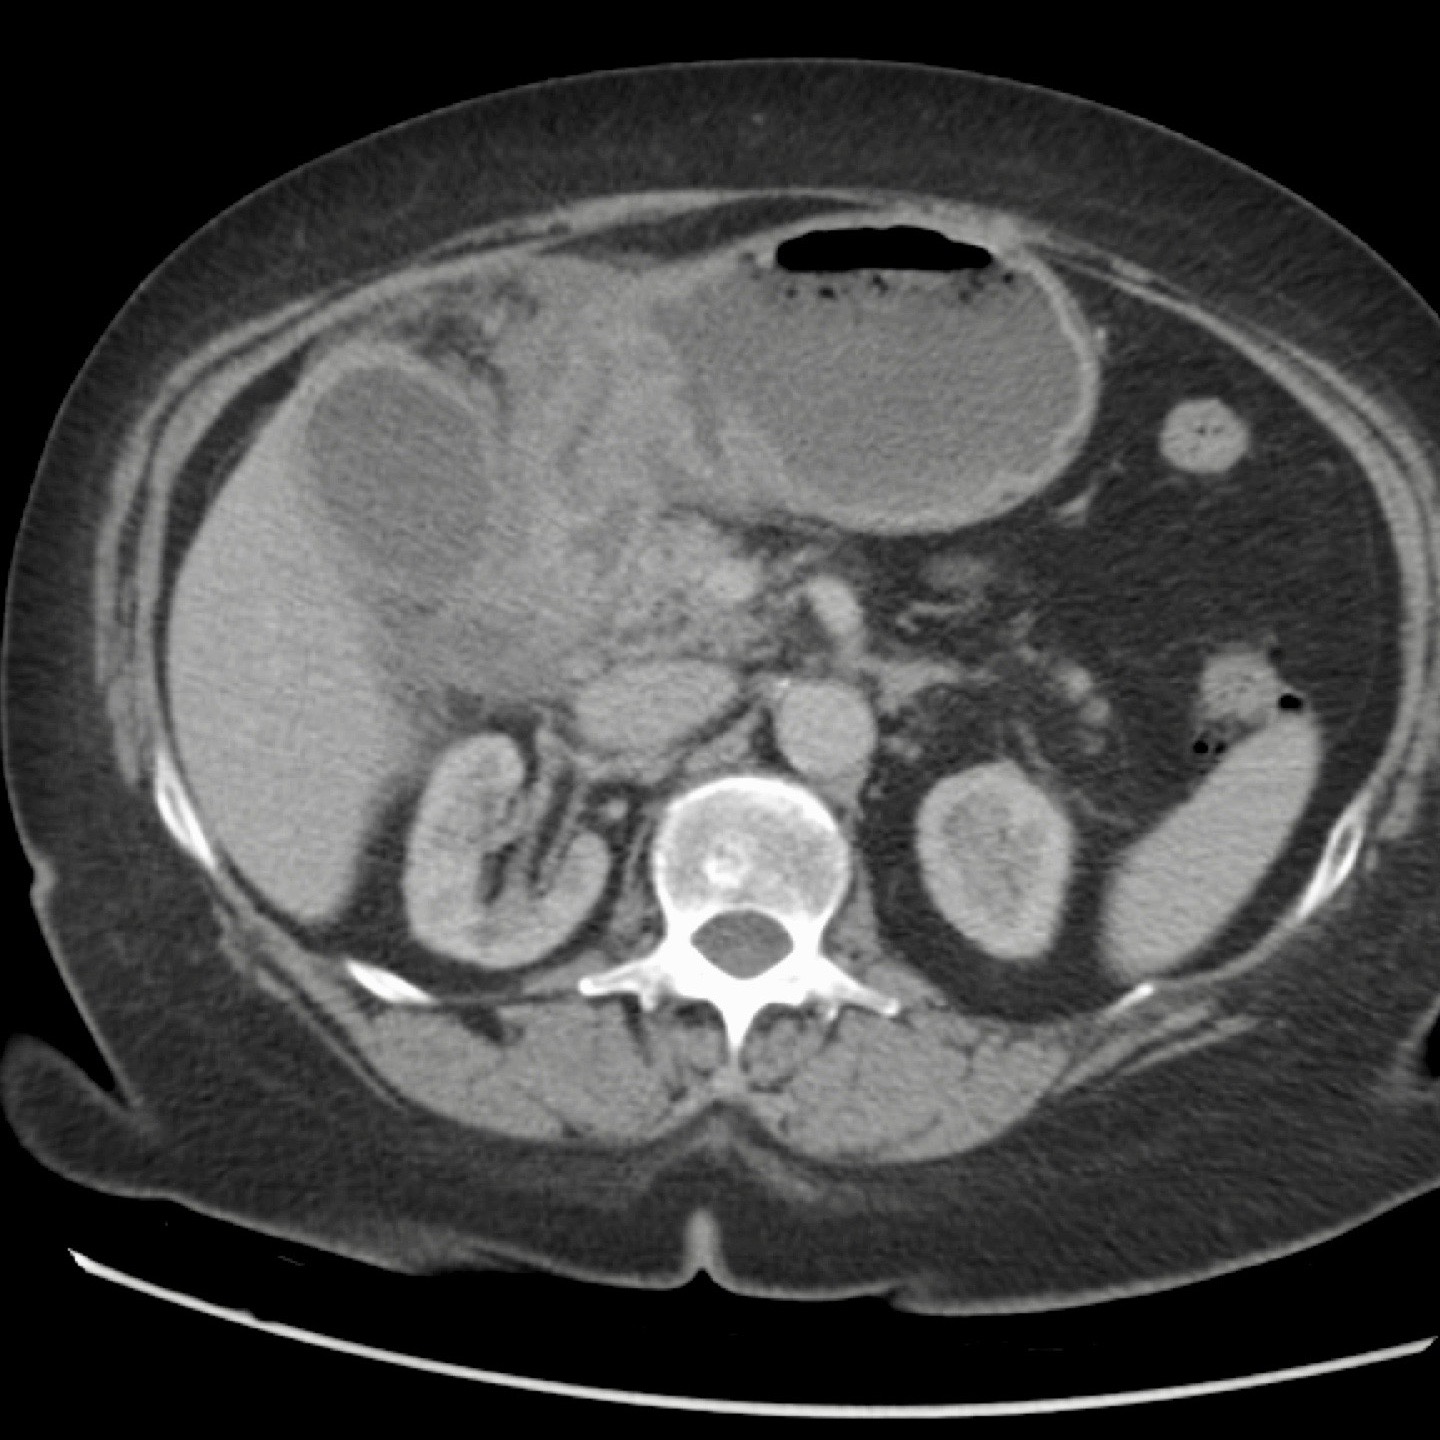

CT trong viêm túi mật cấp

CT có thể rất hữu ích trong các trường hợp siêu âm không cho kết quả chẩn đoán.

Đây là hình ảnh của một bệnh nhân béo phì với đau hạ sườn phải cấp tính trong 6 giờ. CRP 2.

Siêu âm cho thấy túi mật lớn có bùn mật, không quan sát thấy sỏi.

Việc ấn vào túi mật không đáng tin cậy do vị trí cao dưới cung sườn phải.

Không có bất thường siêu âm nào khác.

CT thực hiện cùng ngày cho thấy túi mật lớn với chỉ những thay đổi quanh túi mật kín đáo và không có nguyên nhân nào khác giải thích cho các triệu chứng.

Ngày hôm sau CRP là 105 và CT không tiêm thuốc cản quang lặp lại cho thấy quầng mờ xung quanh túi mật.

Phẫu thuật tiếp theo xác nhận viêm túi mật cấp giai đoạn sớm do sỏi nhỏ trong ống túi mật.